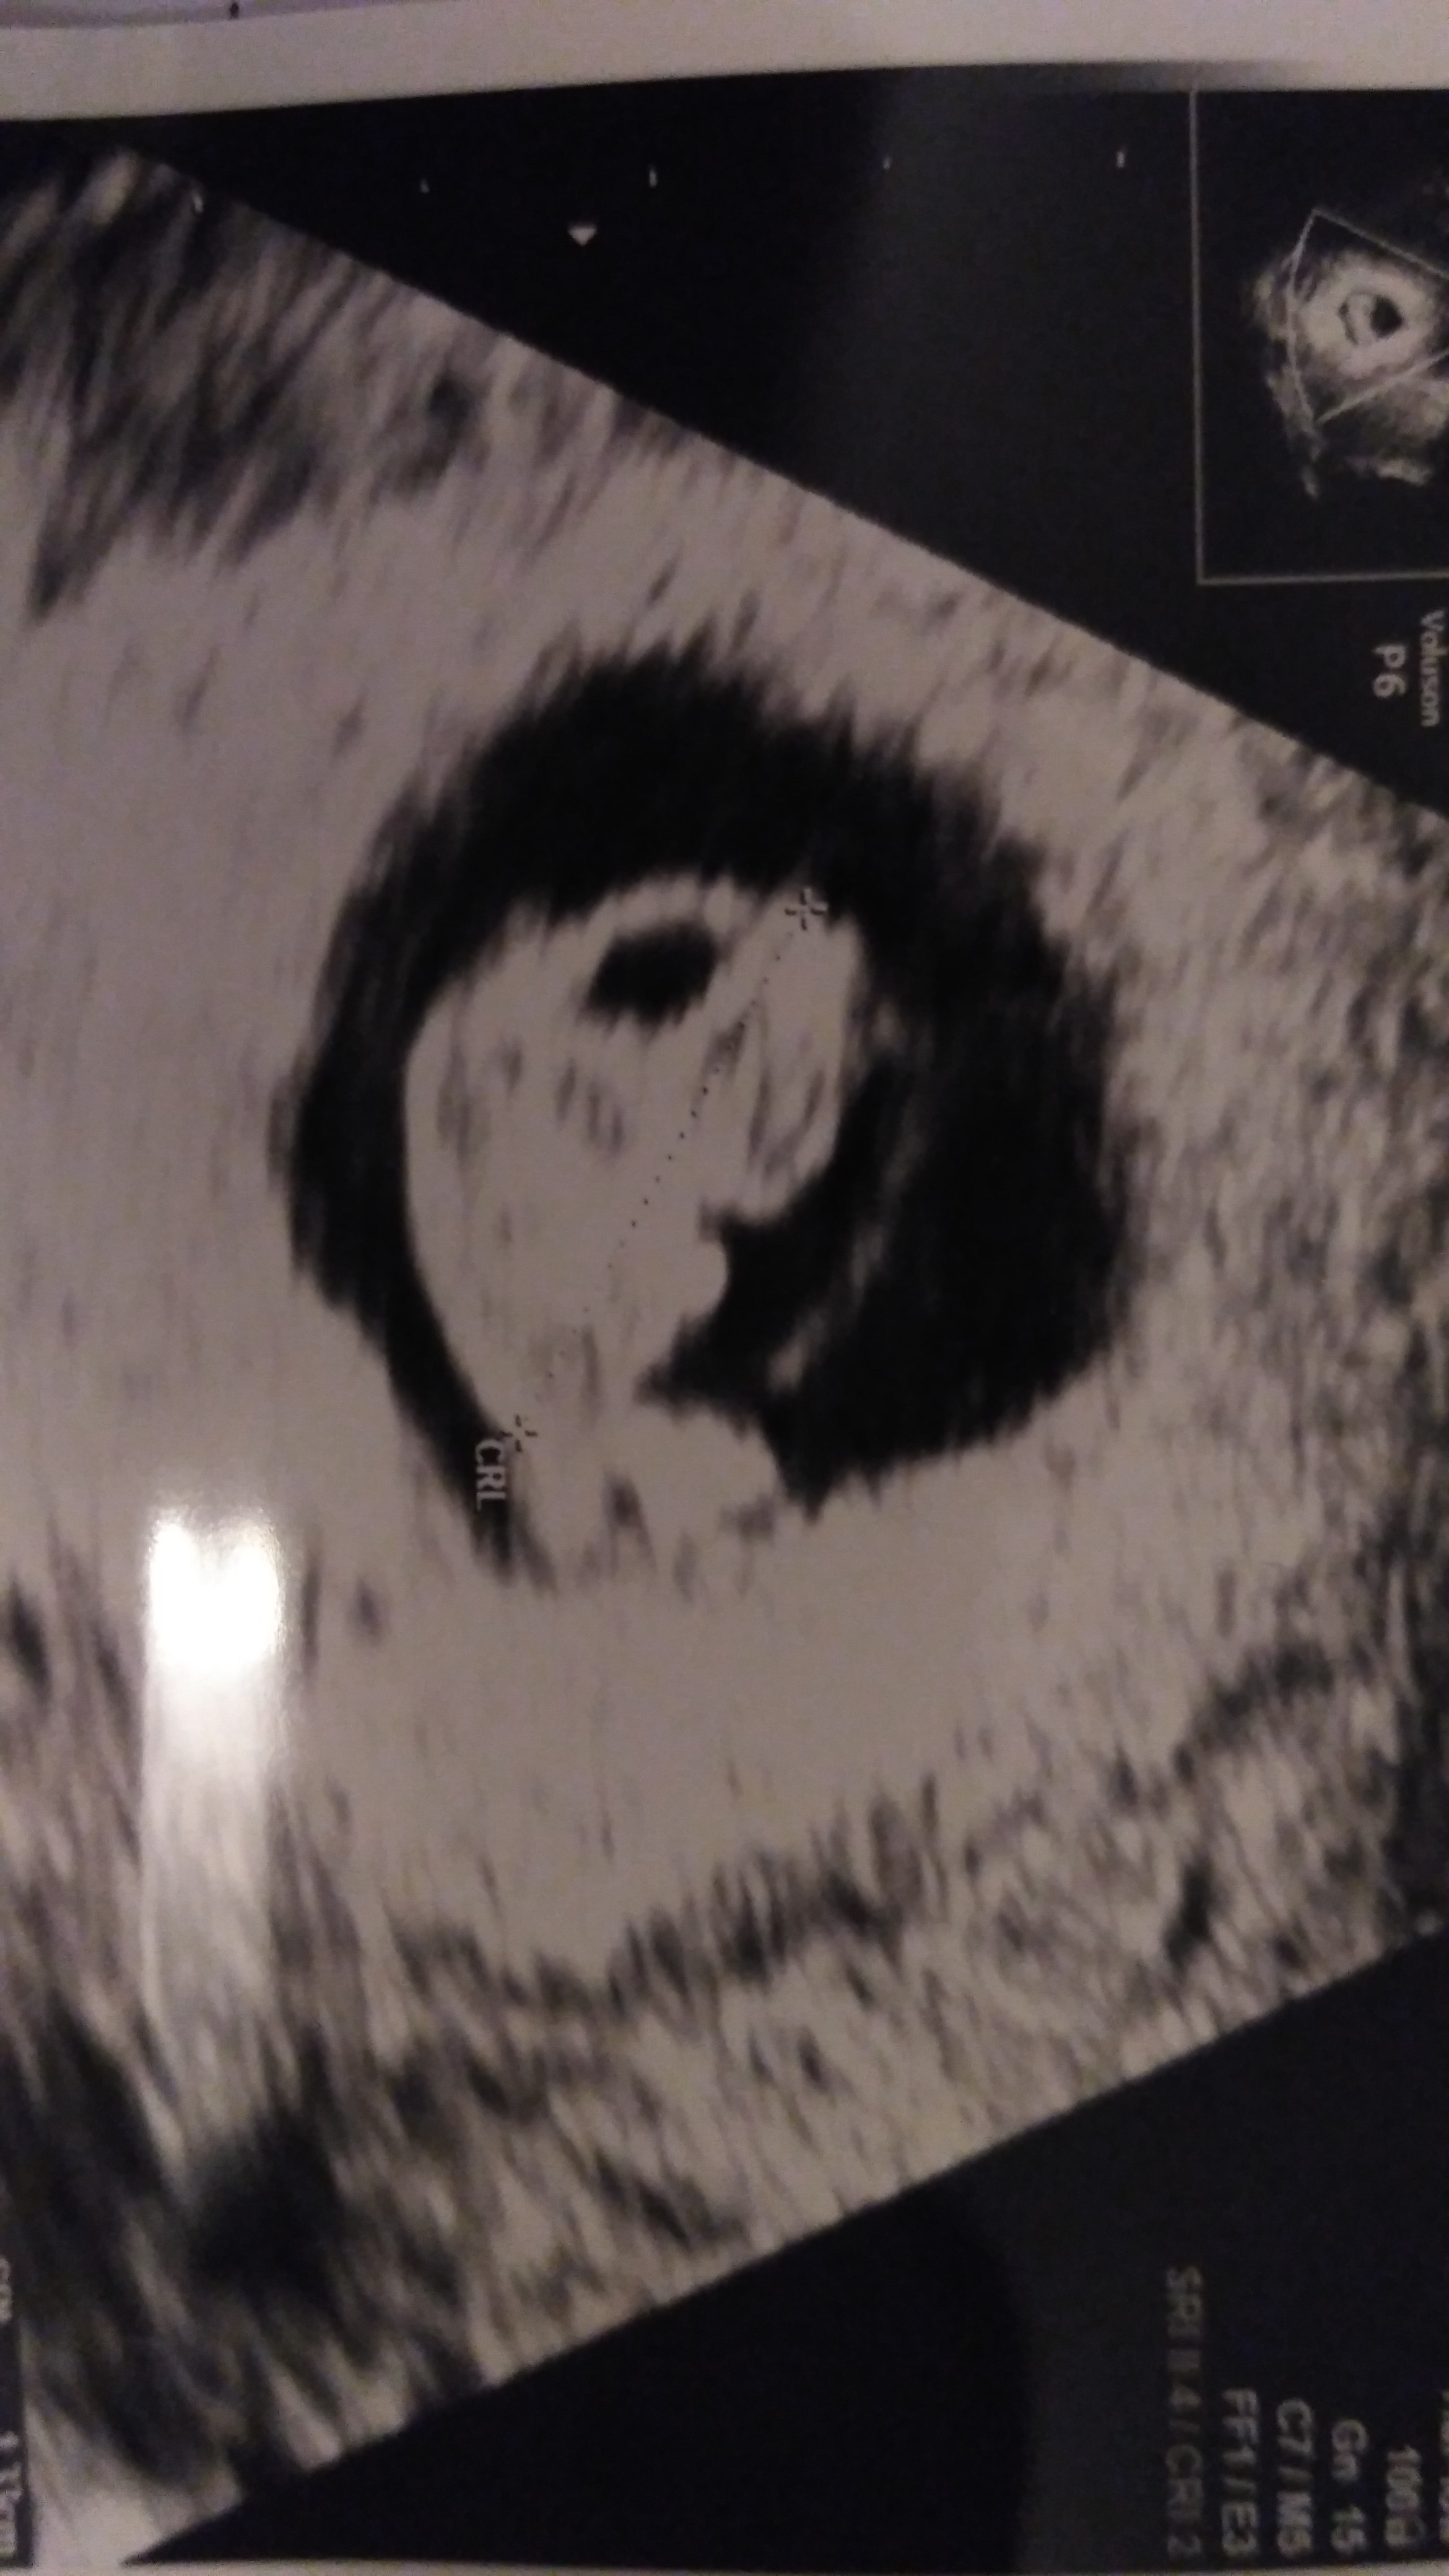

Cześć dziewczyny. Ja już po USG. Jest dobrze. Maluch urósł i dzisiaj mierzy 1,33 cm - 8t+3d (wg. usg 7t+4d). Serduszko bije miarowo. Za 2 tyg. mam iść na badania Pappa i później badania prenatalne. Nie mogę w to wszystko uwierzyć...